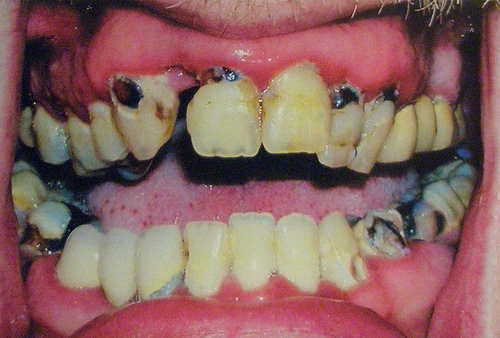

The term meth mouth refers to the profound tooth decay and damage caused by methamphetamine use. As one of the most visible and common aspects of the drug, meth mouth characteristics include broken, discolored, and rotting teeth. Tooth decay often occurs in the cervical regions of the teeth where tooth surface narrows at the gumline. This decay may lead to tooth loss, fractures, and excruciating pain.

The grotesque appearance of meth mouth has been adopted by the media in order to demonstrate the scope of the drug’s effects. Also, anti-drug campaigns use these disturbing images to provoke disgust and deter people from using the drug.

Meth smokers often acquire lesions and burns on their lips and inside their cheeks, while those who snort the drug experience burns in the back of their throat. However, no matter how the drug is consumed, meth decreases one’s ability to fight infection and heal after injury.